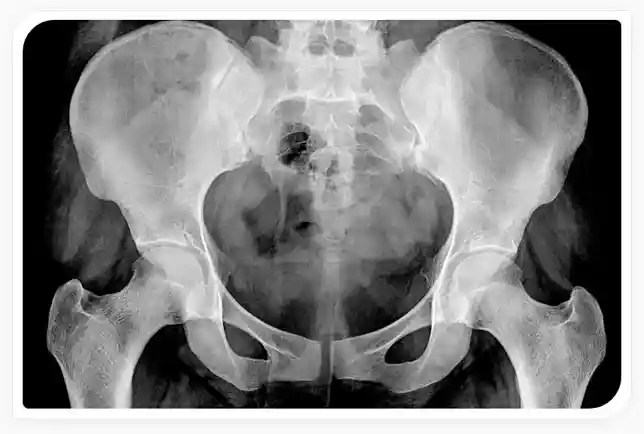

Improvements in imaging technology show that up to 55% of patients with hip or groin pain have labral tears. Athletes who participate in sports such as golf, ice hockey, baseball, softball, soccer, football, long-distance running, and ballet are at higher risk of developing hip labral tears. Figure 1 shows the structure of the hip and an example of a hip labral tear.

Figure 1. Depiction of a labral tear in the hip joint. The hip is composed of the pelvis, the site of the “socket” or acetabulum in which the head of the thighbone or femur fits into. Surrounding the socket is a ring of cartilage called the labrum that keeps the femur firmly seated in the socket joint. An example of a labral tear is shown where the cartilage has pulled away from the bone of the acetabulum. Covering the head of the femur and acetabulum is articular cartilage that can be damaged by chronic labral tears causing osteoarthritis.